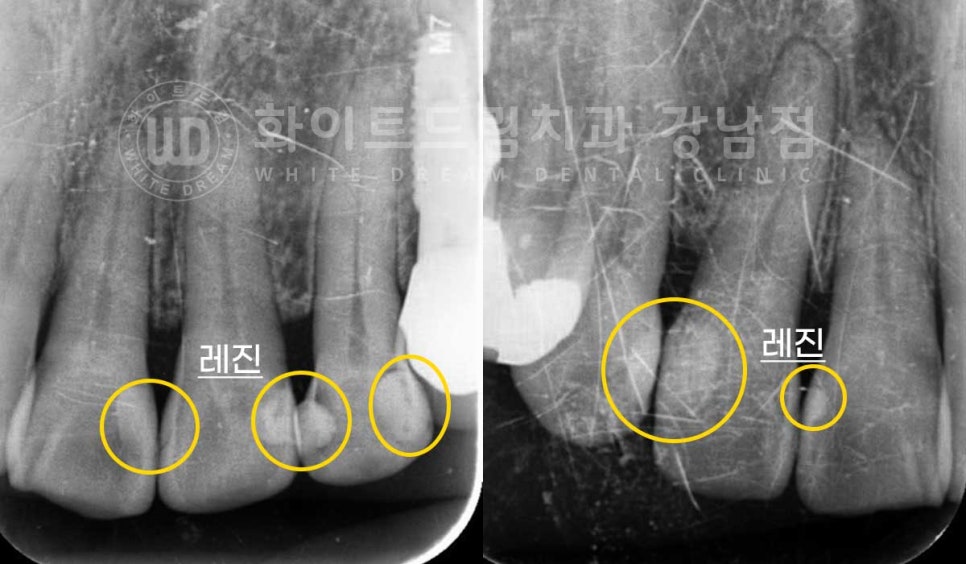

앞니 레진 변색도 신경이 쓰이고 치아 때문에 웃거나 말할 때마다

굉장히 스트레스예요.

직업상 사람을 대면하는 일이 많아 깨끗해 보였으면 좋겠어요.

라는 주소로

치아 개선을 원하셨던 분입니다.

환자분의 초진 구내 사진을 보면 앞니 부분에 마모가 심하게 진행되어 있는 상태입니다.

사진을 자세히 보면 앞니 테두리 부분이 비쳐 보이는 것이 보이실 텐데요.

법랑질이 마모되어서 얇아졌기 때문이랍니다.

이 외에도 레진으로 앞니 치료받은 부위에 변색도 확인이 됩니다.

이 외에도 노화로 인한 잇몸 퇴축으로

블랙 트라이앵글이라는 치아 사이 검은 삼각형의 틈이 발생한 것이 보입니다.